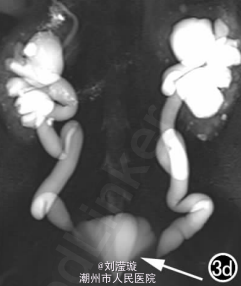

腹部B超示双肾增大,双肾慢性肾病声像;双肾中度积液伴双输尿管上段扩张。 IVPshi双侧输尿管中或下段梗阻。 膀胱造影:经尿道置管后,注射对比剂充盈膀胱,膀胱下半部先充盈,继续灌注对比剂后见膀胱完全显影,膀胱形态异常,呈“倒葫芦状”(图1)。 CT增强扫描行延迟期 MPR重组,见双侧肾盂、肾盏扩张积液;双侧输尿管纡曲、扩张,下端呈鸟嘴样变窄;膀胱变形、体积减小(图2); MRI平扫示双侧肾盂、肾盏扩张积液,双侧输尿管扩张并下端鸟嘴样变窄,盆腔内多量脂肪沉积,分布于膀胱、直肠周围,T1WI、T2WI呈明显高信号,T2WI抑脂像呈稍高信号,膀胱受压变形、体积减小(图3a~c); MRU示双侧肾盂肾盏扩张、积液,双侧输尿管显著纡曲、扩张,下端鸟嘴样变窄,管壁光整,膀胱变形、体积较小、位置抬高(图3d)。